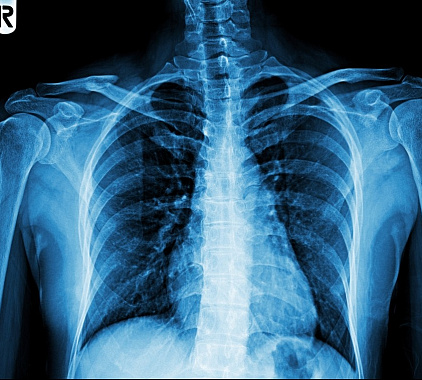

Рентгенография лопатки проводится в нескольких проекциях: прямой и боковой. При необходимости рентгеновский снимок получают в косой, переднезадней проекции. Во время сканирования необходимо сделать вдох и не дышать. Также запрещено разговаривать, без разрешения рентгенолога менять положение тела.

Расшифровка информации является обязательным этапом диагностического исследования и выполняется тотчас после рентгенографии. В протоколе рентгена квалифицированный рентгенолог отражает состояние и анатомические особенности костей и суставов, указывает их важные параметры: структура, форма, размер, расположение, контуры, целостность. Он сравнивает все значения с нормой, диагностирует патологические состояния, выявляет их особенности, описывает состояние смежных областей. На завершающем отрезке специалист пишет подробное заключение.

Органы и ткани отличаются способностью по-разному поглощать рентгеновские лучи. В результате этого возникают достоверные черно-белые изображения, помогающие обнаружить разные патологии. Рентгенологическое исследование лопатки выполняют с целью визуализации трещин и переломов костных структур, остеопороза, некротического поражения, воспалительных процессов, злокачественных опухолей, скоплений метастаз, артроза. Процедура поможет подтвердить наличие артрита, новообразований доброкачественного генеза, аномалий развития, инородных предметов, вывихов и подвывихов.